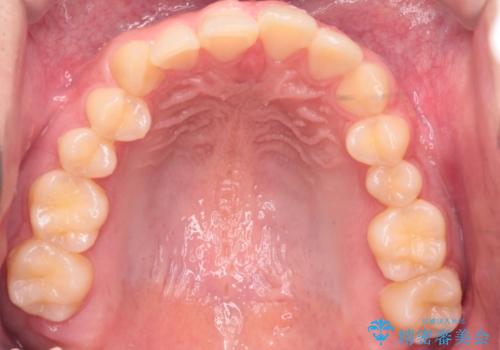

【インビザライン】前歯のガタガタと、前歯の噛み合わせが深いことを治したい。

- 前歯のガタガタと、前歯の噛み合わせが深いことを治したい。との主訴で来院されました。

シミュレーションを用いながら患者様と仕上がりについて相談しインビザラインにて治療を行いました。

仕上げは追加アライナーを数回利用しておこないました。